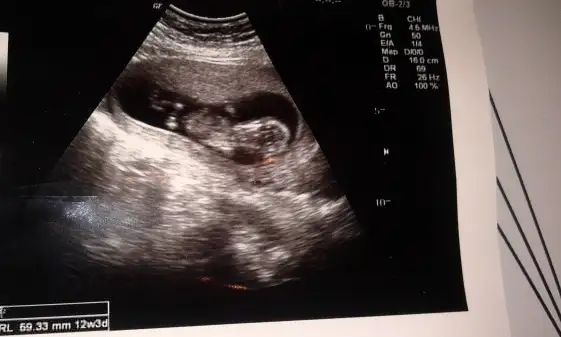

Iste bu resim. Benziyen resimler varsa kiyaslamakmicin

pek tecrubeli degilim..yani cok onemsemeyin ama bence erkekEki Görüntüle 995822 Eki Görüntüle 995823 Eki Görüntüle 995824 Eki Görüntüle 995825

Kizlar yorum yapar kemik yapisina keseye gore..ama nub gormedim sanki ya da tecrubesizligimdennnnbenim bebeğimede bir bakarmısınız? fotografta 12+3 günlük

Senin bebikte kiza benziyobenim bebeğimede bir bakarmısınız? fotografta 12+3 günlük

pek tecrubeli degilim..yani cok onemsemeyin ama bence erkek

nub buyuk geldi banaaa..kizlar duzeltsinler ama bence erkek

Kesine yakin kiz diyorum